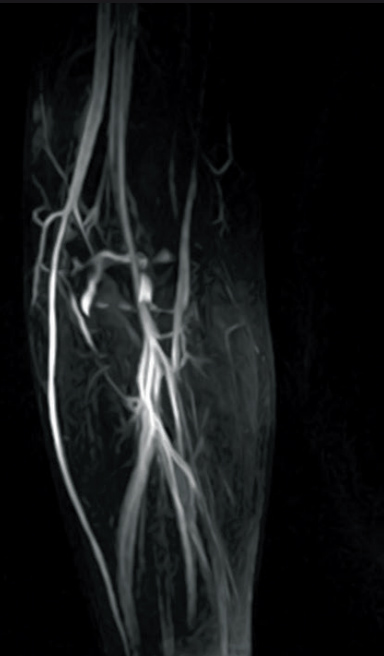

Respiratory-gated MIP image